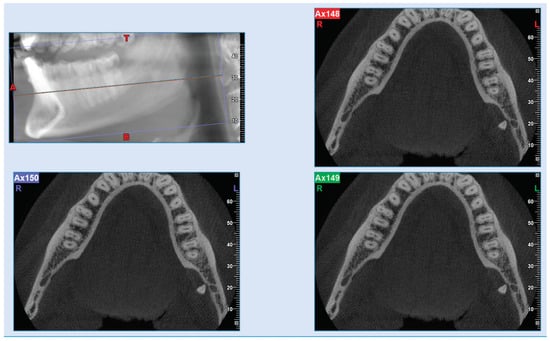

2.4. Radiographic Documentation